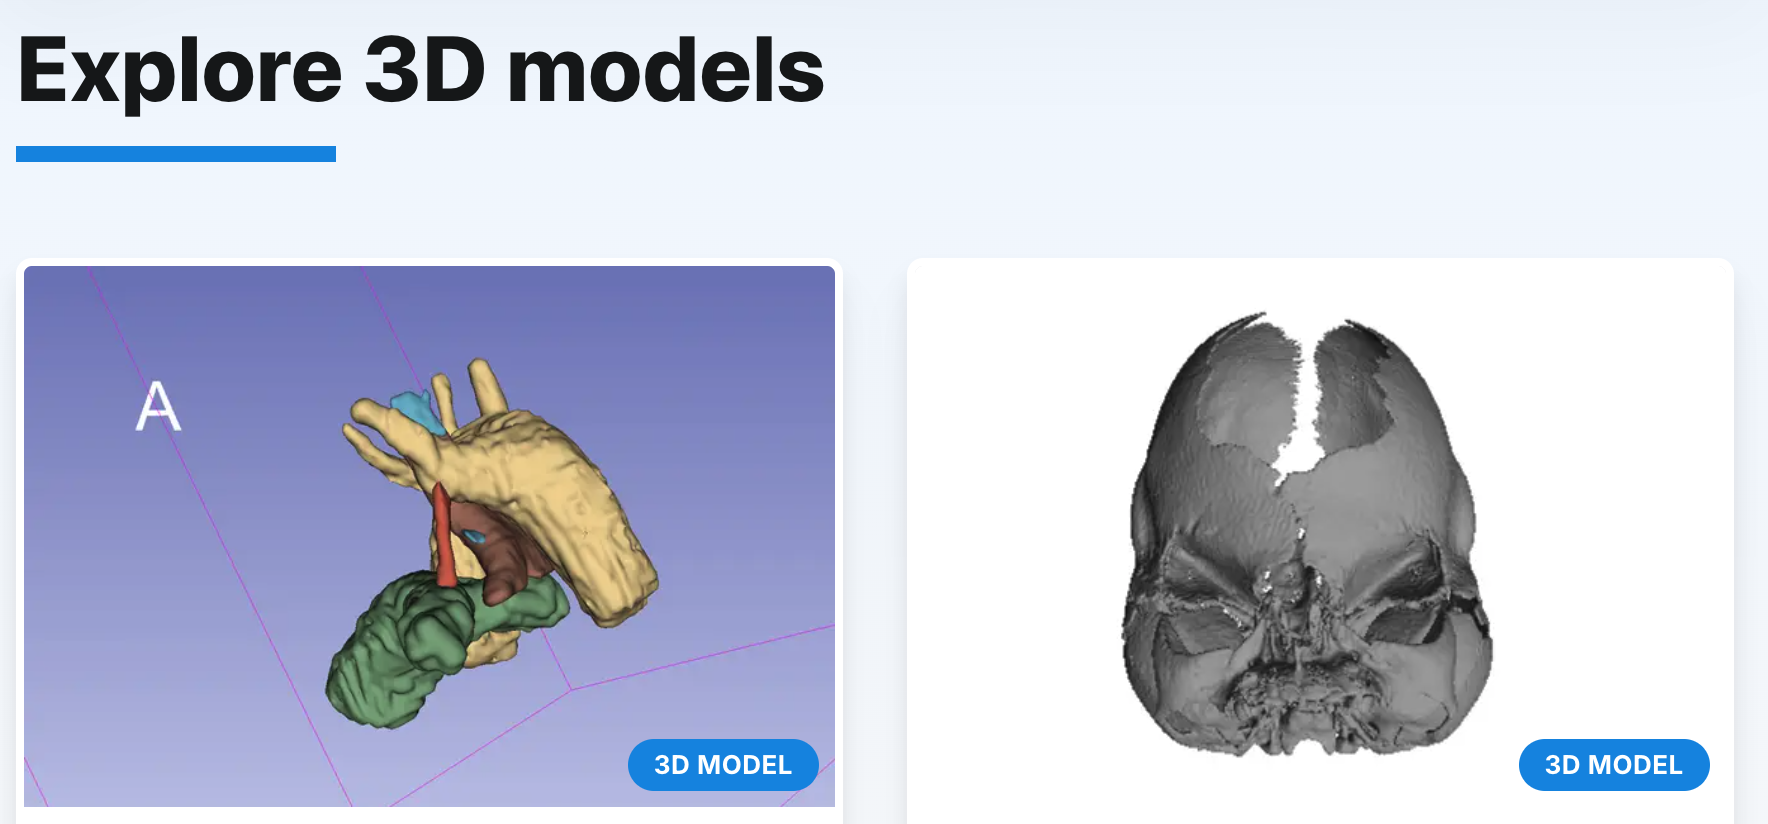

Lékařská fakulta Masarykovy univerzity spustila nový web, který nabízí volně dostupná data pro 3D tisk anatomicky přesných modelů. Studenti, pedagogové i lékaři si tak mohou sami vytisknout například kosti, orgány nebo celé výukové trenažéry. Projekt má sloužit nejen k lepší výuce anatomie, ale i k praktickému využití v klinickém prostředí.

Na rozdíl od většiny podobných platforem, které fungují na komerční bázi, je brněnský portál veřejně přístupný a zcela zdarma. Každý model je navíc doplněn metodikou a garantován odborníkem, který odpovídá za jeho přesnost a vhodnost. Často jde o pedagogy či lékaře, kteří sami definují potřeby výuky nebo chirurgických postupů a následně ověřují, že výsledný model odpovídá realitě i praktickému použití.

Databáze v současné chvíli obsahuje zhruba sedm desítek nejrůznějších modelů od kostí přes vnitřní orgány až po specializované trenažéry. Výhodou vlastní výroby je nejen kvalita, ale i cena: některé pomůcky vznikají za zlomek ceny komerčních produktů. Typickým příkladem je trenažér pro kanylaci pupečníku, který dodavatelé nabízeli v nevyhovující podobě, a proto si jej fakulta vyvinula sama.

Nový portál má však i širší dopad. Odborníci ze simulačního centra fakulty spolupracují s lékaři například z I. chirurgické kliniky Fakultní nemocnice u sv. Anny. Pomocí dat z CT snímků dokáží vytisknout přesnou kopii zlomené kosti podle zrcadlového obrazu zdravé strany. Chirurg si tak může předem natrénovat samotný zákrok, naplánovat umístění destiček či šroubů a vyzkoušet, jak bude rekonstrukce vypadat.